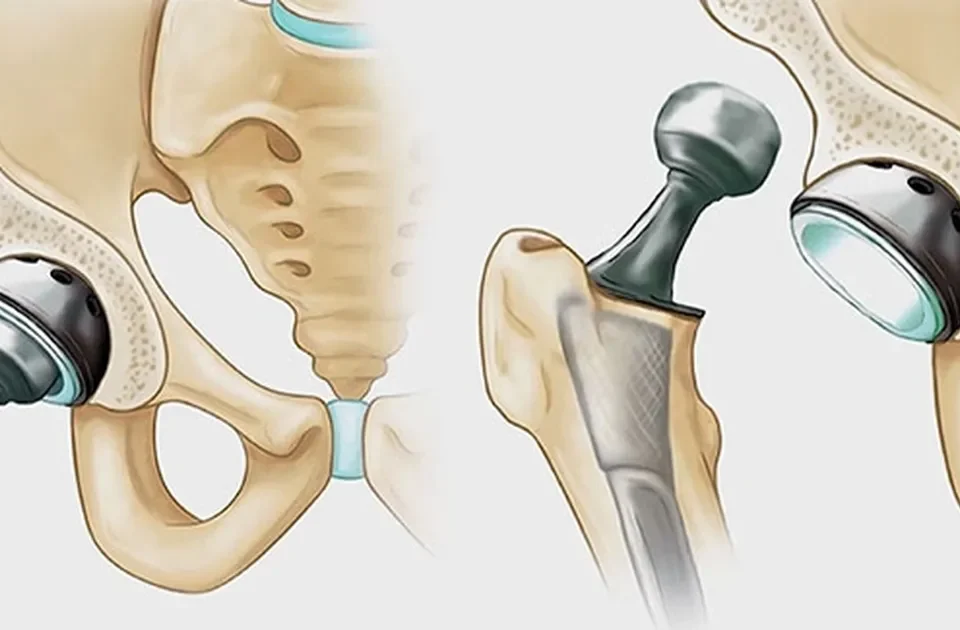

- نکروز آواسکولار

نکروز آواسکولار

نکروز آواسکولار، که به عنوان استئونکروز نیز شناخته میشود، مرگ سلولهای استخوانی به دلیل وقفه در جریان خون به بافت استخوان است. استخوان، به عنوان یک بافت زنده، برای ترمیم خود و حفظ سلامت خود به جریان خون مداوم نیاز دارد. هنگامی که جریان خون مختل میشود، بافت استخوان نمیتواند مواد مغذی دریافت کند، به مرور زمان ضعیف میشود و در نهایت فرو میریزد. فرو ریختن ناشی از آن باعث تخریب سطح مفصل و درد شدید میشود.

این بیماری که بیشتر در مناطقی مانند لگن، زانو، شانه، فک و مچ پا دیده میشود، میتواند علائمی مانند درد استخوان لگن، زانو، فک و پا ایجاد کند. نکروز آواسکولار میتواند به دلیل آسیبهای تروماتیک (مانند شکستگی یا دررفتگی)، استفاده طولانی مدت از دوزهای بالای کورتون یا مصرف بیش از حد الکل رخ دهد.